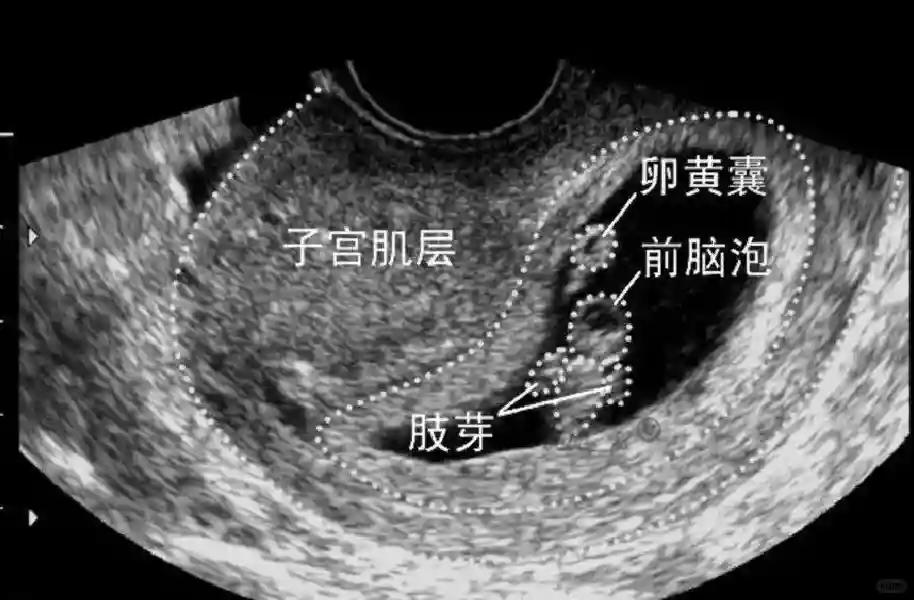

2️⃣卵黄囊:是妊娠囊内第一个解剖结构,直径<7mm。表现为小环状,中央为无回声,囊壁薄,内透声好。卵黄囊位于胚胎旁胚外体腔内。卵黄囊通常在孕5-6周时出现,5-10周稳步增长,一般不超过7mm,至12周消失。妊娠囊的大小与卵黄囊之间有一定关系,妊娠囊平均直径> 8 mm 时,经阴道超声均应显示卵黄囊,妊娠囊平均直径> 18 mm 时,经腹超声均应显示卵黄囊。

3️⃣胚胎:胚胎通常在6-7周时可以为超声显示,起初为胎芽,表现为卵黄囊一侧局部组织增厚,达到1 -2 mm 时才有可能为超声测量出来。达4-5mm时可见胎心搏动,相应孕周为6-6.5周,妊娠囊大小为13-18mm。胚芽长度≥7㎜时仍未见心管搏动,提示胚胎停止发育。胚胎的出现和妊娠囊直径的关系:妊娠囊直径> 16 mm 时,经阴道超声应显示胚胎。妊娠囊直径> 25 mm 时,经腹超声均应显示胚胎。